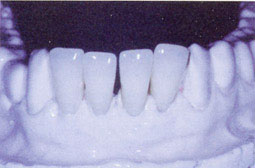

Une jeune patiente de 20 ans consultant le service d'orthodontie pour une béance antérieure causée par la succion du pouce (Fig.2). L'examen clinique révèle une mobilité des 4 incisives antéro-inférieures. L'examen radiologique montre une alvéolyse terminale (Fig.3). 3ème cas clinique : Une patiente de 28 ans adressée par le service de prothèse conjointe pour la réalisation d'une prothèse immédiate. L'examen clinique montre le port d'un bridge provisoire ayant comme piliers la 12 et la 21 et remplaçant la 11. Ce bridge en résine porté pendant longtemps a causé l'inflammation de la gencive marginale et une mobilité des piliers (Fig.4). L'examen radiologique montre une lyse importante de l'os alvéolaire (Fig. 5).